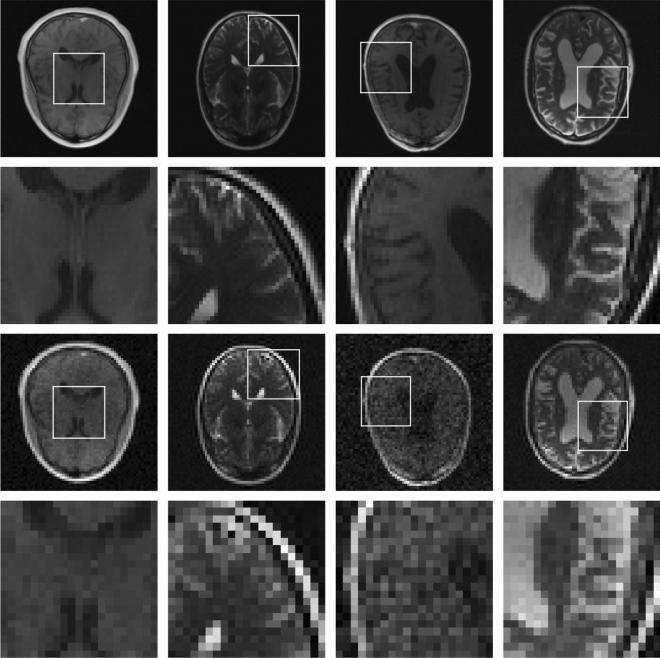

Low-field MRI scanners are significantly less expensive than their high-field counterparts, which gives them the potential to make MRI technology more accessible all around the world. In general, images acquired using low-field MRI scanners tend to be of a relatively low resolution, as signal-to-noise ratios are lower. The aim of this work is to improve the resolution of these images. To this end, we present a deep learning-based approach to transform low-resolution low-field MR images into high-resolution ones. A convolutional neural network was trained to carry out single image super-resolution reconstruction using pairs of noisy low-resolution images and their noise-free high-resolution counterparts, which were obtained from the publicly available NYU fastMRI database. This network was subsequently applied to noisy images acquired using a low-field MRI scanner. The trained convolutional network yielded sharp super-resolution images in which most of the high-frequency components were recovered. In conclusion, we showed that a deep learning-based approach has great potential when it comes to increasing the resolution of low-field MR images.

低磁场磁共振成像扫描仪的价格明显低于高磁场磁共振成像扫描仪,这使得它们有可能使磁共振成像技术在全球范围内更容易获得。一般来说,使用低磁场磁共振成像扫描仪获得的图像的分辨率相对较低,因为信噪比较低。这项工作的目的是提高这些图像的分辨率。为此,我们提出了一种基于深度学习的方法,将低分辨率、低磁场的磁共振图像转换为高分辨率的图像。我们使用一对带有噪声的低分辨率图像及其无噪声的高分辨率图像对训练卷积神经网络进行单图像超分辨率重建,这些图像来自公开的 NYU fastMRI 数据库。然后,我们将这个网络应用于使用低磁场磁共振成像扫描仪获取的噪声图像。训练好的卷积网络生成了清晰的超分辨率图像,其中大部分高频成分都得到了恢复。总之,我们表明,基于深度学习的方法在提高低磁场磁共振图像的分辨率方面具有很大的潜力。